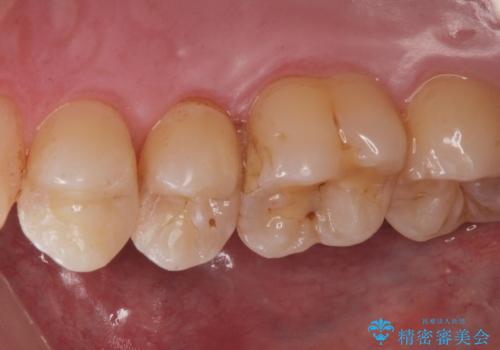

歯と歯の間の虫歯(コンタクトカリエス)

- 虫歯がないかチェックしてほしいとの事で来院。

レントゲンで歯と歯の間に虫歯(コンタクトカリエス)があったので

拡大鏡下で虫歯を全て除去して、e-maxインレーにて治療しました。